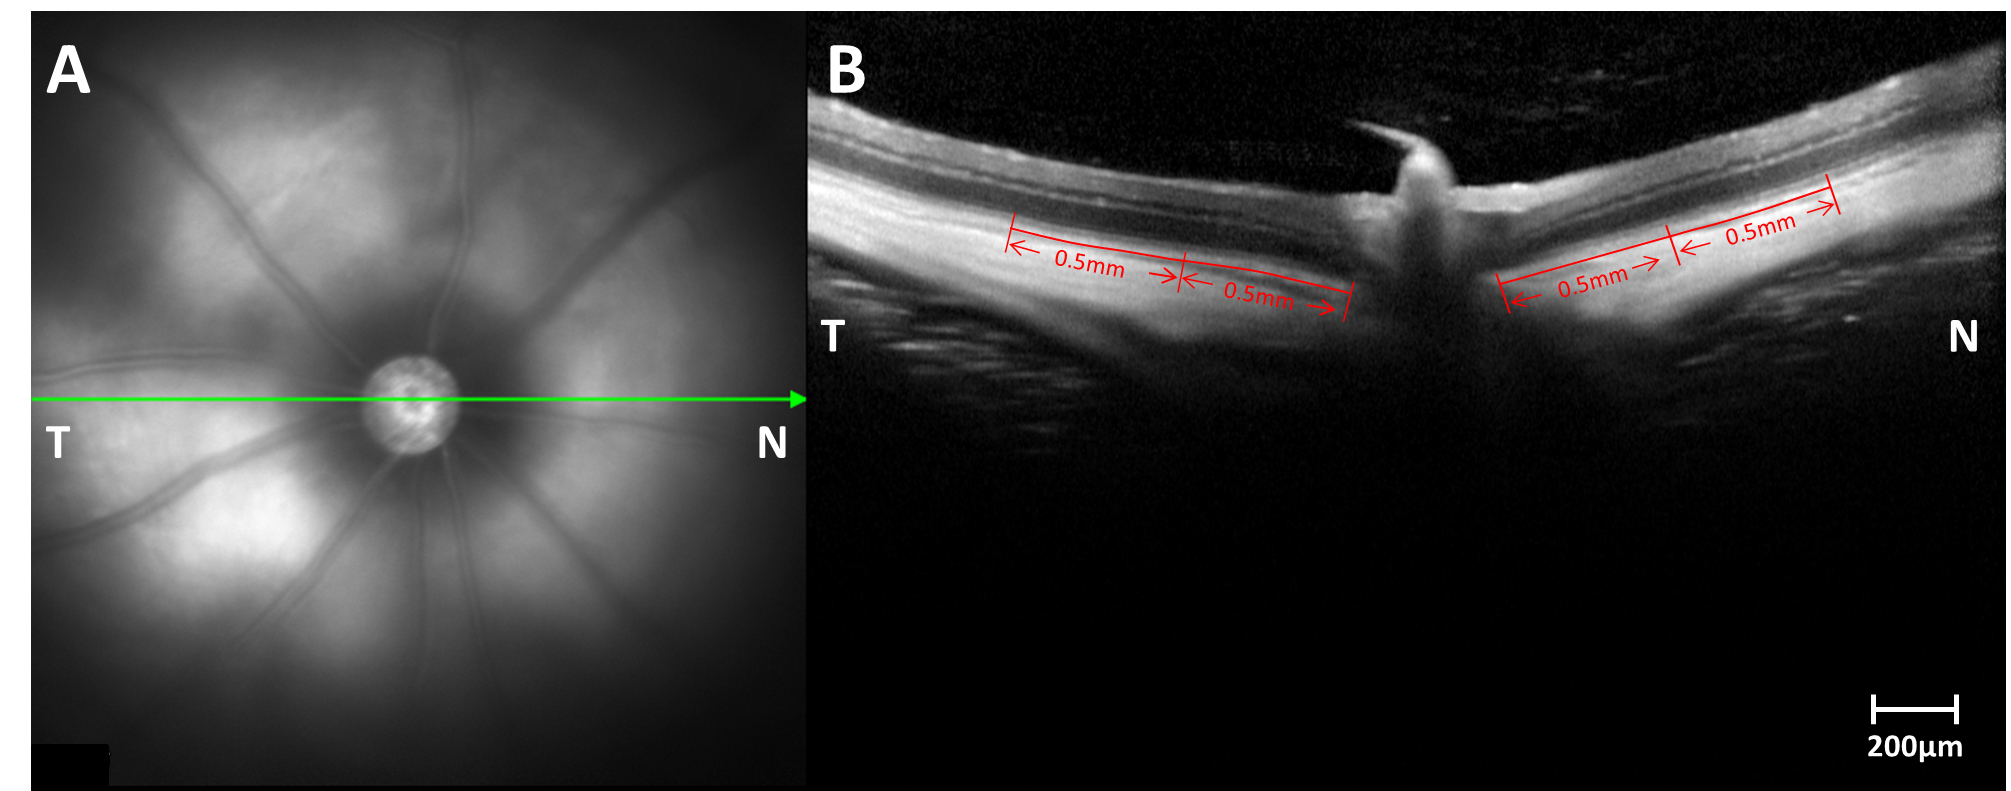

Figure 1. The locations of the retinal thickness were measured and analyzed using coronal OCT. A: The corresponding fundus photography micrographic pictures of optical coherence tomography (OCT). B: OCT coronal images and the locations of retinal thickness analyzed at 0.5 mm and 1.0 mm intervals from the optic nerve.

Scale bar: 200 μm. N, nasal; T, temporal.